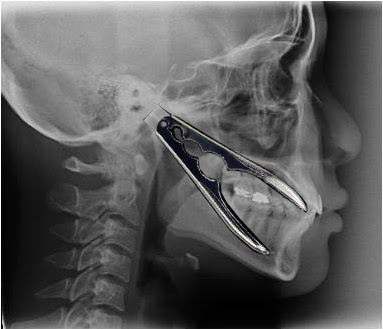

Okluzal Analiz Metodlari Ve T Scan Dr Serdar Gozler Pdf Ucretsiz Indirin

Digital Okluzyon Analizi Cene Eklemi Istanbul Dishekimleri Odasi Facebook